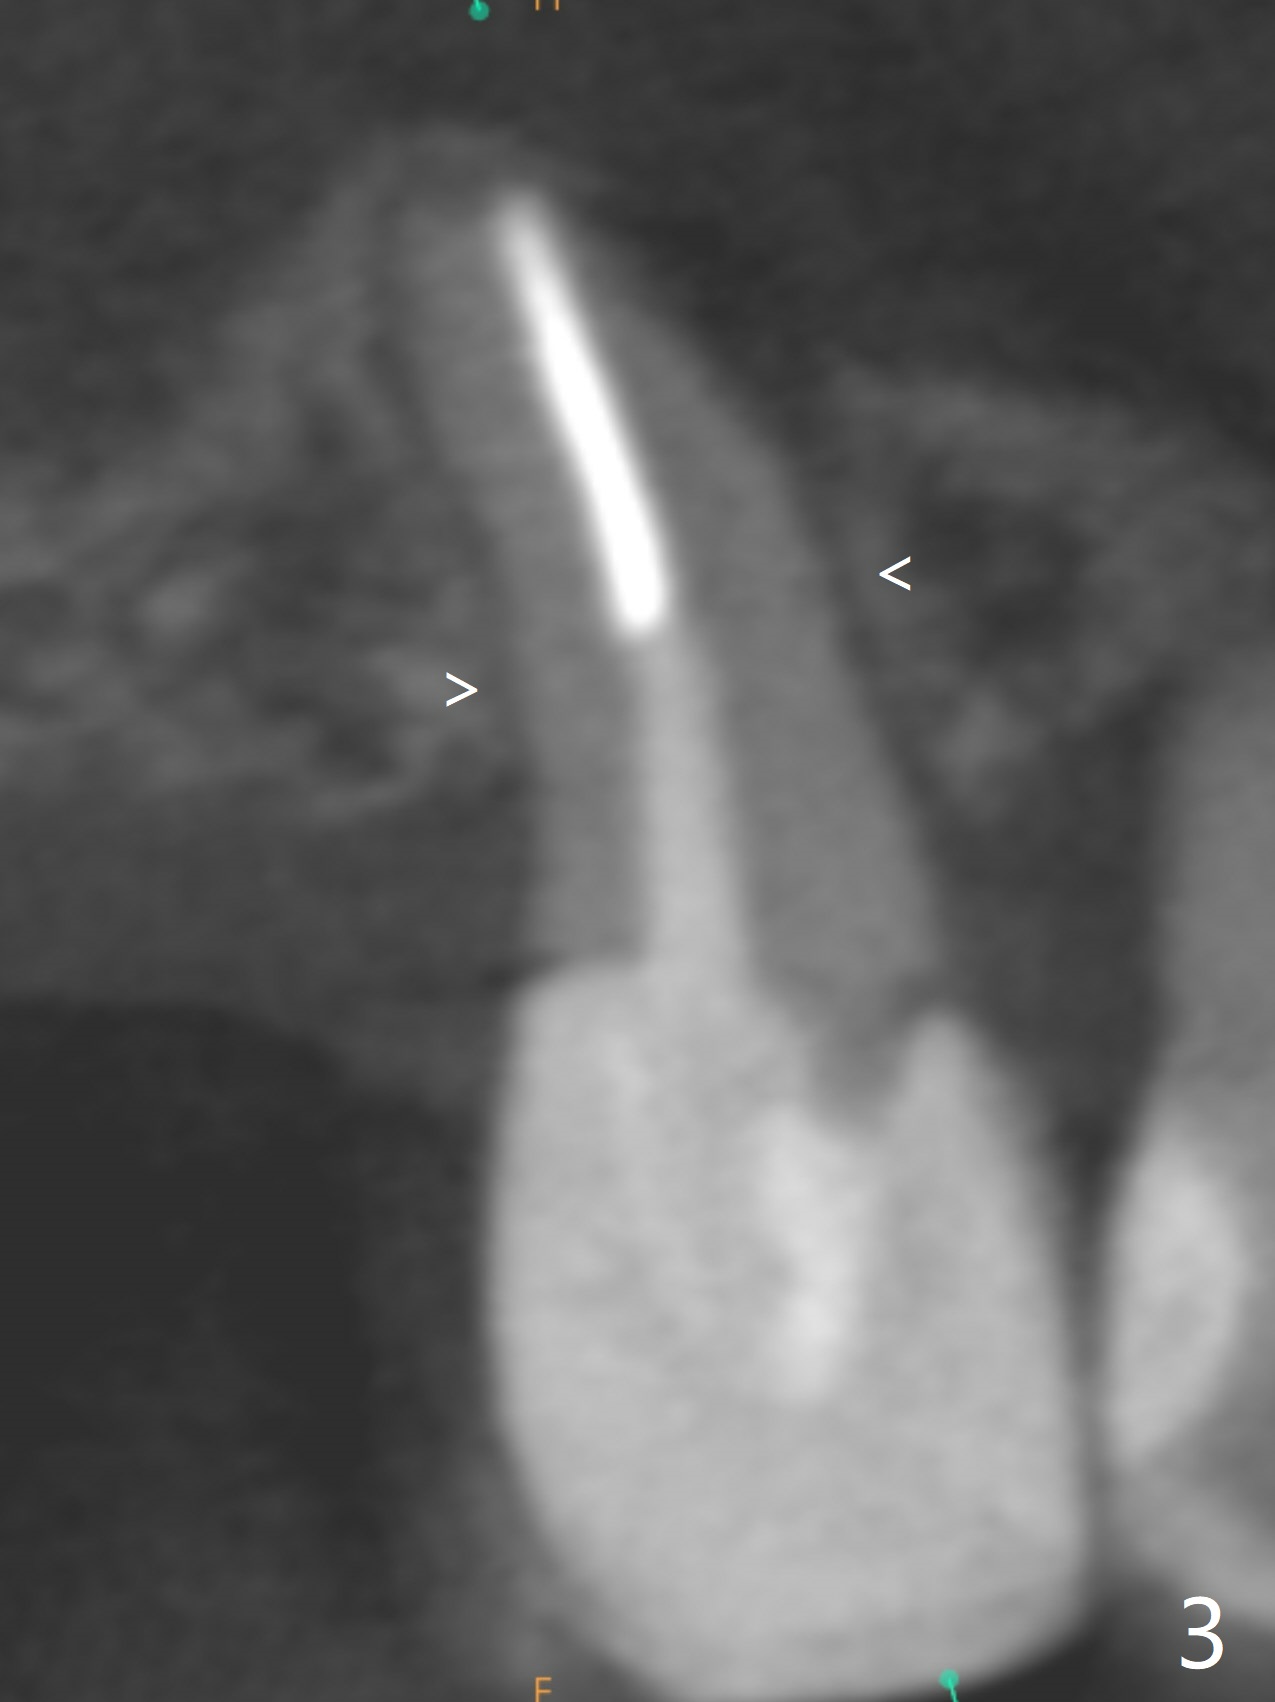

A 71-year-old woman with RPDs develops a fistula buccal to the tooth #5 (Fig.1). The buccal root seems to be fractured as indicated by arrowheads in Fig.2,3 (coronal and sagittal sections). The diagnosis of the fracture is confirmed by the abrupt change in density shown in Profile and the coronal section in Fig.4. Three-dimensional image demonstrates bone over the root surface of the teeth 6 and 8 (Fig.5 *), as compared to no bone over the the buccal root of the tooth #5. Due to financial constraint, the buccala root amputation is proposed as a treatment option. Is it viable?